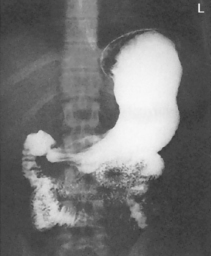

The air-barium distribution within the stomach and large intestine changes with various body positions. By knowing these distribution patterns, one can determine in which body position a radiograph was taken. Air always rises to the highest levels, and the heavy barium settles to the lowest levels (air is black, barium is white).

The fundus is located more posteriorly; therefore in the supine position it would be the lowest portion of the stomach and would be filled with barium.

In both prone and erect positions, the fundus would be filled with air as seen on the drawings below, with a straight air-barium line on the erect.

The ascending and descending portions are located more posteriorly, and thus more of these parts in general would be filled with barium (white) in the supine position and with air (black) in the prone position.

This much separation of barium and air occurs generally only with double-contrast barium-air studies.

Air-fluid levels would be seen in the erect position in which the air would rise to the highest position in each of the various sections of the large intestine, as shown in the accompanying figure.